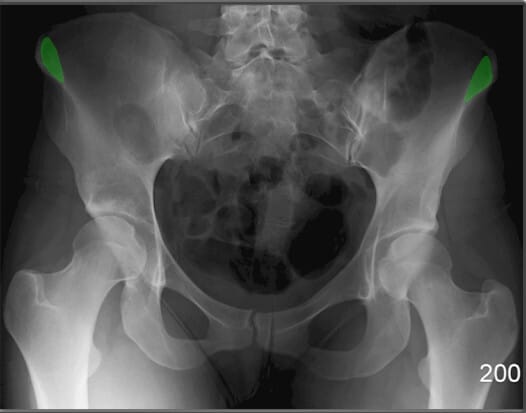

전상장골극 (ASIS, Anterior Superior Iliac Spine)

| 전상장골극 (ASIS, Anterior Superior Iliac Spine) |

| ✅ 장골의 앞쪽 윗부분에 돌출된 뼈로, AP view에서 골반의 가장 상전방에 대칭적으로 위치합니다. |

| 🔴 표면해부학에서 중요한 구조로 , 골반의 변위를 대략적으로 파악할 수 있습니다. |